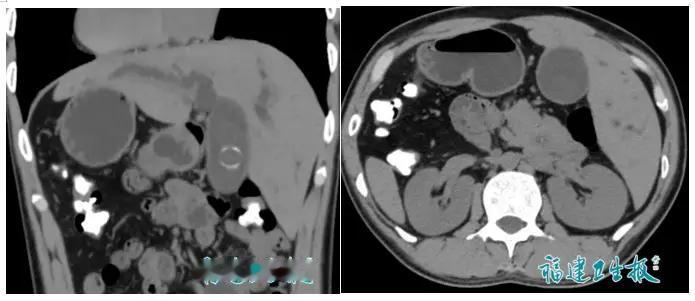

心脏长在右边、肝脏跑左边!福建惊现“百万分之一镜面人”,一场逆向手术揭开生命奇迹背后的医者匠心与人间温情 当CT影像清晰地显示心脏在右侧跳动,肝脏与脾脏如镜像般彻底反转,诊室里的空气仿佛瞬间凝固。这不是科幻电影的情节,而是近日发生在福建医科大学吴孟超纪念医院肝胆外科的真实一幕。一位因腹痛黄疸就诊的陈先生,意外被发现自己竟是全球发生率仅约百万分之一的“完全性内脏反位”者,俗称“镜面人”。更棘手的是,他还并发胆总管结石,一场颠覆常规认知的高难度手术就此拉开序幕。 当地医院看到完全反转的解剖结构影像时,只能无奈婉拒。对医生而言,这如同让习惯右手写字的人突然用左手完成精细书法,每一步操作都需逆向思维,稍有不慎便可能损伤重要血管。陈先生辗转求医的奔波与焦虑,或许只有经历过的人才懂。那种明明病痛缠身却求助无门的茫然,足以击垮许多人的心理防线。然而,生命的韧性总在绝处逢生。 “只要有一线希望,就不能让患者绝望。”李海涛主任医师这句话,成了照亮迷雾的一束光。面对这例罕见病例,医疗团队没有退缩,而是开启了全方位的“逆向备战”。他们联合影像科进行三维重建,在虚拟世界中精准复刻出患者的镜像解剖图;麻醉、护理团队反复演练,将每一个器械传递、每一项监护流程都调整为“反向模式”。这不仅是技术的挑战,更是对医者责任与初心的极致考验。 手术台上,腹腔镜显示屏里的世界是颠倒的。肝脏出现在不该出现的右侧,胆管蜿蜒在陌生的左侧。李海涛医生双手操控器械,仿佛在进行一场精密的镜像舞蹈。他必须暂时忘记数十年形成的肌肉记忆,在反向视野中避开变异血管,精准定位。最终,凭借腹腔镜与胆道镜的双镜联合,团队仅用两小时便成功取净结石,出血量不足一小杯水,且避免了患者术后长期携带引流管的痛苦。 这场手术的成功,远不止于解除一位患者的病痛。它像一面镜子,映照出当代医学在应对罕见复杂病例时,那份敢于突破常规的勇气与精细化协作的力量。它让我们看到,当技术遇上仁心,生命的奇迹便有了坚实的依托。而陈先生术后一周即康复出院的身影,更是对这份匠心最好的致敬。 令人动容的是,新闻评论区成了无数“镜面人”及其家属的倾诉角落。有人分享自己八十多岁父亲同样反位却安康长寿的故事;有人含泪回忆因类似情况早年未能挽回的孩子;更有不少网友自称或亲友是“镜面人”,并调侃体检时总把年轻医生吓一跳。这些真实的声音汇聚在一起,让我们恍然发现,这看似百万分之一的“特殊”,其实连接着无数具体而鲜活的人生。 透过现象看本质,“镜面人”议题之所以触动人心,是因为它触及了我们共同的情感内核——对生命差异的尊重、对医疗突破的期盼,以及在不确定性中对专业与善良的深切渴望。每个人的人生都可能面临某种“罕见”处境,或许是身体的特殊,或许是命运的难题。我们渴望被理解、被接纳,更渴望在困境中遇到那位愿意“多走一步”的守护者。 这场发生在福建的“逆向手术”,与其说是一场技术的胜利,不如说是一次关于信任与希望的温暖传递。它提醒我们,医学的进步不仅是攻克疑难杂症,更是让每一个独特的生命都能被看见、被认真对待。而作为普通人,当我们或家人面临健康挑战时,主动沟通、寻求经验丰富的团队、保持积极信念,本身就是一股强大的力量。 生命的形态或许千差万别,但追求健康与幸福的权利平等而珍贵。愿这份来自手术台前的匠心与温度,能照亮更多看似不同却同样值得被精心呵护的人生旅程。 (来源:综合潇湘晨报、福建卫生报、海峡都市报及网络平台热议内容) 镜面人奇迹 医者仁心